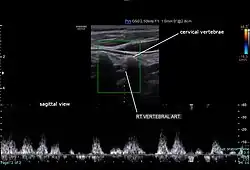

Typically, blood flow velocities in the carotid artery are measured in terms of peak systolic velocity (PSV) and end diastolic velocity (EDV).[15]

Normally, vertebral artery blood flow velocity can be 63.6 ± 17.5cm/s during PSV and 16.1 ± 5.1cm/s during EDV according to a study done by Kuhl et al.[16] Due to vertebral artery dominance, measurements can vary on both sides, for example, another study by Seidel et al. found that the right side had an average of 45.9cm/s and the left side 51.5cm/s during PSV, and 13.8cm/s on the right side and 16.1cm/s on the left side during EDV.[15][17]